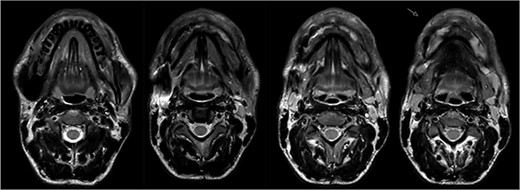

The MRI performed three months after the last pamidronate infusion revealed a significant reduction of enhancement in the mandible with some patchy hypointense areas remaining (Fig. 5).

Magnetic resonance imaging (MRI) 3 months after bisphosphonate therapy. T2 weighting shows the significant reduction of inflammatory activity within the mandible after bisphosphonate treatment.